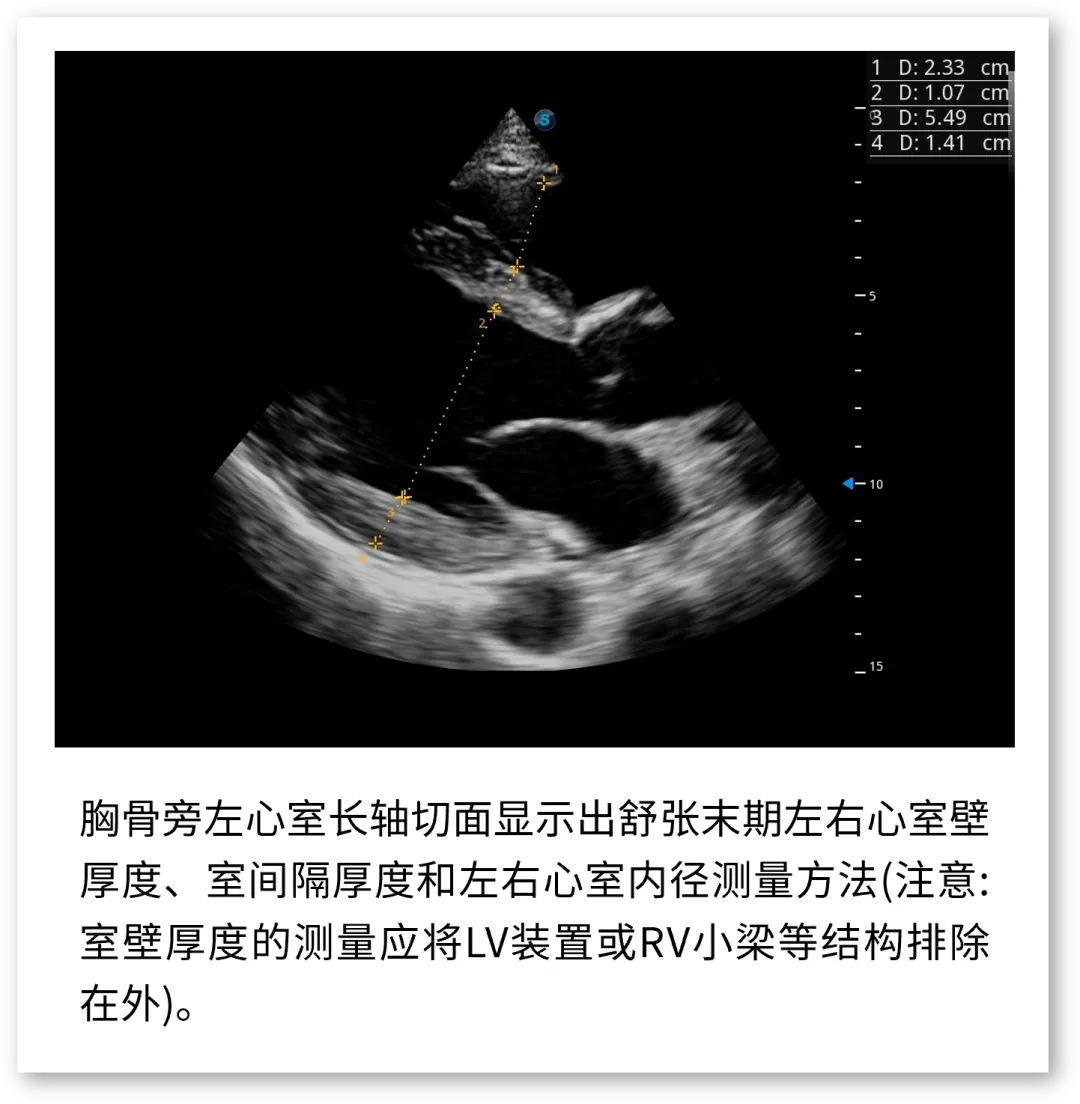

开立医疗联合武汉大学中南医院心血管病医院,将《心脏超声检查规范化中国专家共识 (2024版)》内容与实际临床工作需求融合,精心制作了指南挂图,助力标准采集,规范测量,期待这份实用且高清的工具,能成科室提升超声质效的助手!